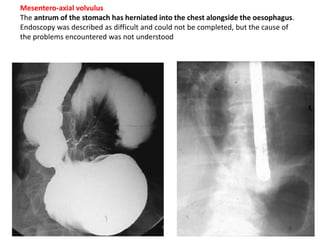

Mesentero-axial volvulus

The antrum of the stomach has herniated into the chest alongside the oesophagus.

Endoscopy was described as difficult and could not be completed, but the cause of

the problems encountered was not understood